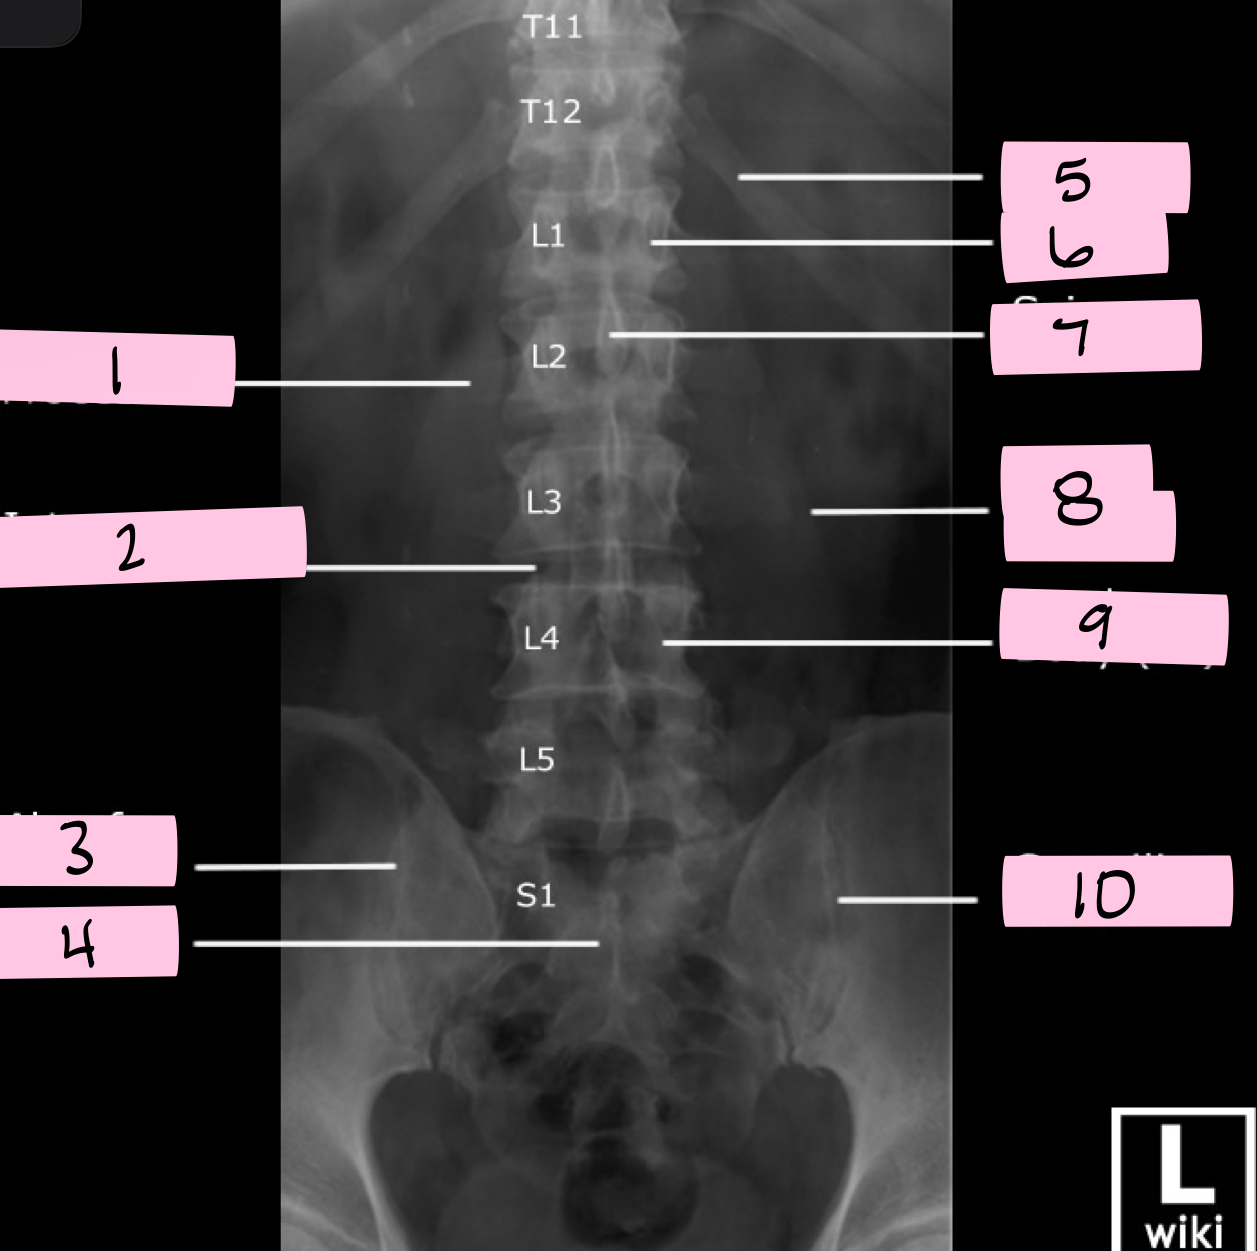

What is 1 pointing to?

Transverse process

What is 2 pointing to?

Intervertebral disk

What is 3 pointing to?

Ala of sacrum

What is 4 pointing to?

Sacrum

What is 5 pointing to?

12th Rib

What is 6 pointing to?

Pedicle

What is 7 pointing to?

Spinous process

What is 8 pointing to?

Psoas muscle

What is 9 pointing to?

Lumbar body (L4)

What is 10 pointing to?

Sacroiliac joint